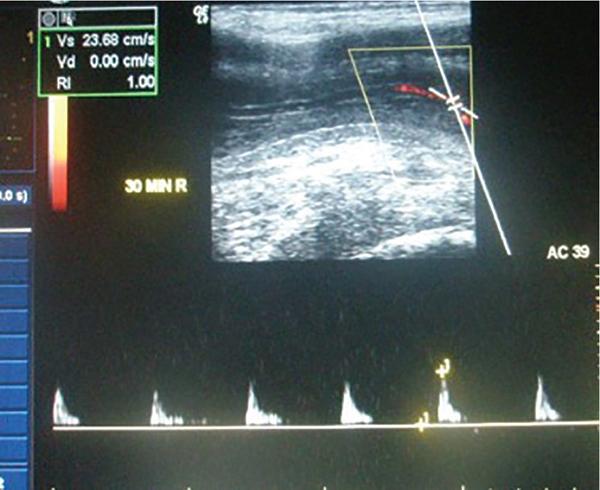

Rijo Mathew Choorakuttil The penis is a superficial, protruding organ that is highly vascularized and composed of several soft tissue structures. Penile pathologies and abnormalities are not uncommon, although they are not usually as well discussed as other organ pathologies. Ultrasound studies are useful in the assessment of penile pathologies and dysfunctions. In this chapter, you will learn about Penile erection is primarily a neurovascular phenomenon, initiated by erection triggers such as imagination, visual, auditory, olfactory, genital and nongenital tactile stimulation. These triggers result in neurologic signals transmitted through the parasympathetic nerves and release of nerve-derived nitric oxide (nNOs) and vasodilatation. Due to the vasodilatation, endothelium-derived nitric oxide (eNOs) is produced, which continues to produce vasodilatation if the erection triggers are continuously operating and facilitated only in the presence of a hormonal and psychological environment. Sexual stimulation initiates the release of neurotransmitters from the cavernous nerve terminals and relaxing factors from the endothelial cells result in arteriolar smooth muscle relaxation. Increased blood flow and relaxation of the cavernous smooth muscle result in rapid filling and enlargement of sinusoids against the TA. The compression of the subtunical venular plexuses lead to a significant occlusion of venous outflow. Blood is trapped within the cavernosa and raises the intracavernosal pressure (ICP). This leads to full erection. The base of the corpus cavernosum, which is blood filled, is compressed by the ischiocavernosus muscle during sexual activity. The penis enters the rigid erection phase with temporary cessation of the inflow and outflow. Emissary veins get contracted between the circular and oblique fibres of tunica to maintain the blood filled in sinusoids in erection. Detumescence begins as the trabecular smooth muscle contracts and venous channels open, expel the trapped blood and restore flaccidity. The penis is an organ given to intermittent tumescence that is often related to sexual stimulation. Priapism is a persistent tumescence unrelated to sexual stimulation that usually lasts more than 4 h. Priapism can be categorized as arterial and venous types. Arterial priapism is less common that venous or ischemic priapism. Ischemic priapism, caused by decreased or absent venous drainage is a medical emergency that needs immediate attention. Arterial or high-flow priapism is often seen in fistula formation or cavernosal metastasis of a solid tumour and is caused by arterial influx that is increased and often uncontrolled. Arterial-lacunar fistula seen in arterial priapism may directly extend to the cavernosal tissue and bypass the helicine arteries. Colour Doppler ultrasound (CDUS) studies reveal a characteristic colour blush and turbulent high-velocity flow. Low-flow or ischaemic priapism occurs as a failure of tumescence characterized by the absence of cavernosal blood flow. Low-flow priapism commonly reveal a lack of CA blood flow or with a very high-resistance flow pattern in the CA in CDUS. Progressive curvature and shortening of the penile shaft are the characteristic of Peyronie’s disease. It may be associated with a palpable nodule and may lead to pain during erection and dyspareunia. Penile ultrasound imaging studies may show multiple calcified nodules along the tunical envelope of the cavernosum and signs of veno-occlusive erectile dysfunction (ED) (Fig. 11.13.1). Improvements in real time spatial resolutions and contrast have helped in the preoperative assessment of Peyronie’s disease and the quantification of penile fibrosis. Sonoelastography and contrast-enhanced penile ultrasound studies can also help to provide more information on penile pathology. Sonoelastography techniques are useful to differentiate and detect noncalcified fibrous plaques. ED may be psychogenic, organic or of mixed aetiology. Reliable estimates on the exact prevalence of ED is scarce, although some studies have reported a prevalence of 12% in men aged above 18 years and 25%–30% in men aged between 60 and 70 years and 52% in the Massachusetts Male Aging Study. Nearly 70% of men may suffer from ED at some time during their life and 30% of men may experience one episode of ED in a given month. Estimates suggest that an estimated 152 million men worldwide were present with ED in 1995 and this may increase to nearly 322 million men with ED by 2025. ED can cause stress, affect self-image and cause lack of confidence as well as relationship problems. ED can also suggest an underlying health condition that needs treatment. ED is one of the earliest manifestations of endothelial dysfunction and peripheral vascular and cardiovascular disease in men. Vascular insufficiency and ED secondary to excessive venous leakage is the most common cause of organic ED. Persons with ED of vascular causes have more markedly impaired endothelial and smooth muscle functions compared with patients having similar risk factors but no ED. The prevalence of vascular comorbidities increased with ED severity suggesting that ED may be a prognostic marker for overall health. ED is an important legal question especially in cases or marital consummation, separation and divorce and rape and sexual assault. Doppler ultrasound studies may be useful in the determination of ED in such cases. The treatment of structural penile diseases depends on the underlying causes. Medical therapy may help in patients with moderate disease while surgical correction may be needed for persons with severe penile deformity. It is possible to minimize the diagnosis of indeterminate cause with proper ultrasound techniques and interpretations. The determination of psychogenic ED is important and appropriate counselling and psychotherapeutic processes may help to alleviate symptoms in psychogenic ED. Penile trauma is relatively rare, but not uncommon and has a reported incidence of 1 in 175,000 hospital admissions. Rupture of the TA and the corpus cavernosa, often seen in the setting of an erect penis during vigorous sex, direct trauma, masturbation, falls, forceful manipulation and rolling over in bed during an erection, can lead to penile fractures (PF). PF may need emergency surgical repair. On the other hand, blunt penile injury without disruption of the TA or urethral injury may be treated conservatively. The TA, which has a normal thickness of 2 mm in a flaccid penile state elongates during erection with a reduction of thickness to 0.25 mm. A transverse rupture of the corpus cavernosum can lead to a curved or bent penis. Penile fracture generally occurs in the proximal or middle shaft and results in a transversal tear. Radiologic evaluation for PF includes retrograde urethrography, cavernosography, magnetic resonance imaging (MRI), US and CD ultrasonography. Retrograde urethrography and cavernosography are invasive and with high rates of false-negative findings. MRI is an excellent imaging modality with multiplanar capability and excellent tissue contrast but is expensive and not widely available everywhere. US is ideal to evaluate patients with penile trauma and can be routinely used in an emergency. It is a noninvasive method and should be performed with a high-frequency (7–12 MHz) linear transducer, anatomic orientation and ample gel to provide high-quality images. Ultrasound studies that use high-resolution greyscale imaging, high-frequency broadband traducers, in isolation or with colour and pulsed-wave Doppler are the initial tests for the evaluation of penile trauma. Colour duplex Doppler ultrasound (CDDU) is performed using a high-resolution probe – range of 10 to 16 MHz positioning the probe at the crus (at the level of penoscrotal junction) and at mid penis (1/2 distance between the penoscrotal junction and the coronal sulcus). Vasoactive drugs (intracavernosal injection of papaverine 60 mg (n = 700) or prostaglandin E-1 20 mcg, n = 1576), audiovisual sexual stimulation (AVSS) and/or tactile sexual stimulation (TSS), in a quiet room with aesthetic and erotic environment and without any external disturbances are part of the assessments as appropriate. The assessments are done in the presence of a team that included andrologist, radiologist and sex therapist. Sampling factors, gate placement and angle corrections are optimized for consistent, reproducible results. The penis is scanned from its ventral surface using longitudinal and transverse views. Evaluation is done with the penis in a flaccid state and after the intravenous injection of the vasoactive drugs. CDUS with spectrum analysis is performed with tuning for a slow-flow setting. Penile bodies present with intermediate echogenicity and homogeneous echotexture in the flaccid state. After a cavernosal injection, sinusoidal distension begins in the central portion of the cavernosa and is less echogenic than the outer portion. The filling phase reveals several fine echogenic grids of the sinusoidal interfaces in the corpus cavernosum. The penile septum is a back attenuated echogenic structure that may obstruct the evaluation of the dorsal penis and the TA. The sampling location and angle can influence the measurement of the peak systolic velocity (PSV) of the CA (Fig. 11.13.2). Colour Doppler signals are used to guide spectral sampling of the CA at the origin on the base of the penis, at the site where CA angles posteriorly toward the crus. This helps to standardize velocity measurements. It is preferable to apply the angle correction cursor or the steering box (Fig. 11.13.3).